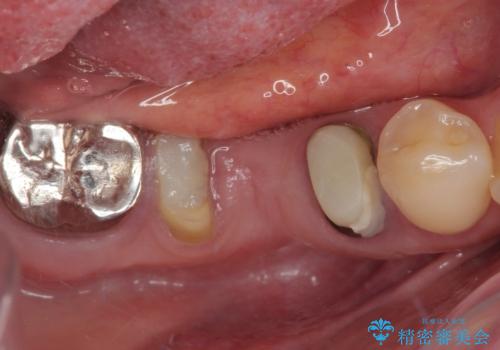

左下小臼歯は根管治療で対応する予定でしたが、診断のために歯肉を開いたところ頬側に垂直破折が認められたため、抜歯即時埋入インプラントによる補綴治療を選択することとしました。

右下は大臼歯部の歯は抜歯即時埋入インプラントにて、手前の歯は保存して補綴治療を行うこととしました。

インプラント埋入時に十分な安定値を得ることができたため、速やかに仮歯を装着し、最小限の通院回数で治療を終えることができました。